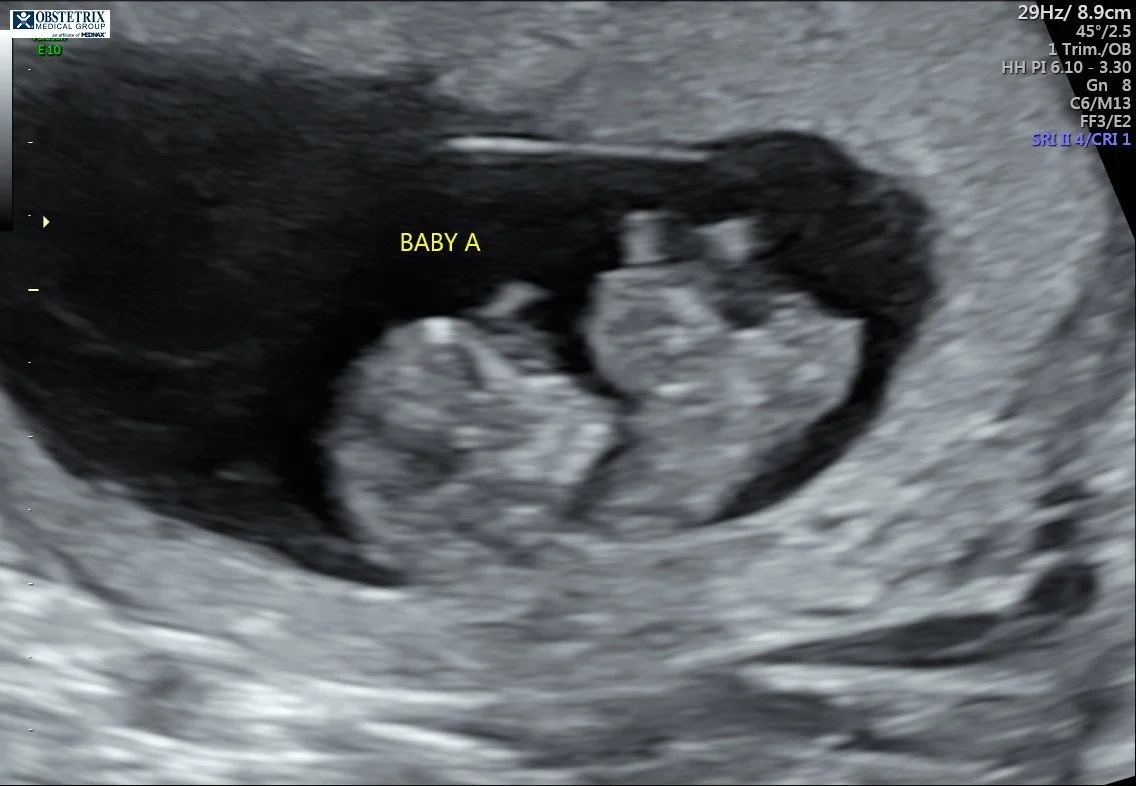

At 10 weeks, the MFM Dr saw something on Baby A and told us it could be one of 3 three things. I don't remember the third, but it was for sure that it was either omphalocele or gastroschisis. I had scheduled my blood test already for the following week and had a relook at the ultrasound at 13 weeks. This was when it was confirmed Baby A had omphalocele. The blood test came back, and everything else looked good. It was very scary as I went down the Google hole and read terrible things.

Thirteen week ultrasound, when omphalocele was confirmed.